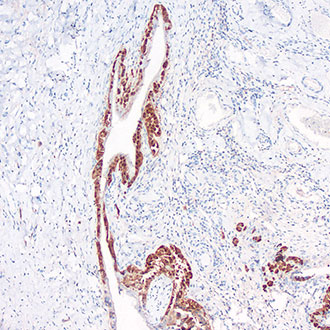

CK19

CK19 -